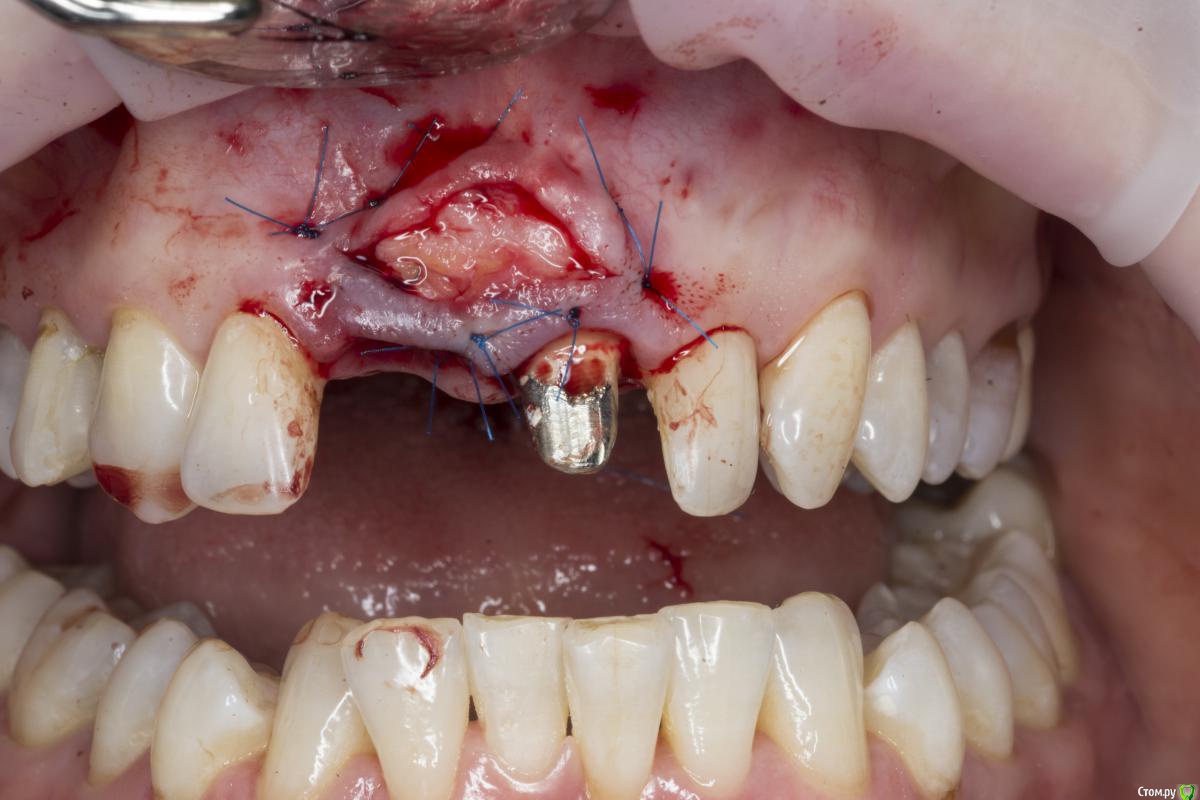

Александр07 Опубликовано 26 июня, 2020 Автор Поделиться Опубликовано 26 июня, 2020 Коллеги, скидываю фото проделанной работы, прошло около 1.5 мес, есть результат, спасибо за помощь, если какие то замечания /советы есть пишите 4 Ссылка на комментарий

Irouil Опубликовано 26 июня, 2020 Поделиться Опубликовано 26 июня, 2020 Справились одним трансплантом в итоге?) Ссылка на комментарий

колесников Опубликовано 26 июня, 2020 Поделиться Опубликовано 26 июня, 2020 (изменено) Здравствуйте! Не видел этого поста раньше,бегло посмотрел. Определенно проблема была в выборе высоты абатмент и объёме реставрации. Вы убрали композит максимально в основании-это хорошо,но абатмент оставили прежний. Следовало взять новый с высотой уступа 4-5 мм. Край коронки пришеечный следует опустить ниже,иначе десна опять отскочит. И переход слелайте на плавный а под углом,так называемый балкон. Потом будет что отдавить. По Масана сосочек сделали это хорошо и правильно,но с такой реставрацией опасно,мало место лоскуту. К счастью кажется все живы. На данном этапе рекомендую пропилить балкон и этим ограничится. Изменено 26 июня, 2020 пользователем колесников Ссылка на комментарий

Александр07 Опубликовано 27 июня, 2020 Автор Поделиться Опубликовано 27 июня, 2020 Справились одним трансплантом в итоге?)Два, один под сосочек с бугра второй вестибулярно с неба Сст 1 Ссылка на комментарий

Александр07 Опубликовано 27 июня, 2020 Автор Поделиться Опубликовано 27 июня, 2020 Здравствуйте! Не видел этого поста раньше,бегло посмотрел. Определенно проблема была в выборе высоты абатмент и объёме реставрации. Вы убрали композит максимально в основании-это хорошо,но абатмент оставили прежний. Следовало взять новый с высотой уступа 4-5 мм. Край коронки пришеечный следует опустить ниже,иначе десна опять отскочит. И переход слелайте на плавный а под углом,так называемый балкон. Потом будет что отдавить. По Масана сосочек сделали это хорошо и правильно,но с такой реставрацией опасно,мало место лоскуту. К счастью кажется все живы. На данном этапе рекомендую пропилить балкон и этим ограничится.С высотой да, выше надо было , на постоянной учтём , по балкону принцип понятен, - больше места для транса, но все же времянки рекомендуют плавными делать, без резких переходов, поэтому такой вопрос если выпиливать максимально места для тр-та то когда переводить временную коронку на плавный дизайн , через месяц где-то когда транс приживется и стабилизируется первично ? Ссылка на комментарий

колесников Опубликовано 27 июня, 2020 Поделиться Опубликовано 27 июня, 2020 Через 2 недели. Но можно и месяц Ссылка на комментарий